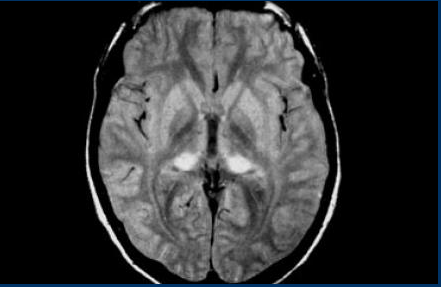

CADASIL As imagens do FLAIR mostram achados clássicos em CADASIL - hiperintensidades da substância branca confluentes com infartos lacunares e envolvimento dos lobos temporais anteriores